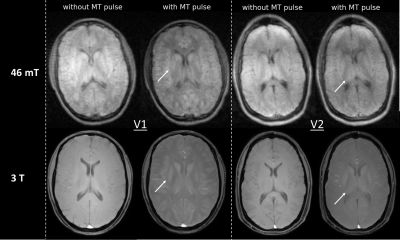

49 In-vivo Magnetization Transfer neuroimaging at 46 mT

Beatrice Lena1, Thomas O'Reilly1, and Andrew Webb1

1C.J. Gorter MRI Center, Radiology Department, Leids Universitair Medisch Centrum, Leiden, Netherlands

Motivation: Here, we exploited the Low SAR in low-field MRI to study magnetization transfer (MT) , and potential to enhance brain tissue contrast, in particular between white and gray matter (challenging at low-field).

Goal(s): The study aimed to identify suitable MT settings and explore MT contrast in-vivo at 46 mT.

Approach: MT settings were optimized to minimize direct saturation and maximize MT contrast. With this setup, we scanned five volunteers at 46 mT and acquired additional 3T scans for two participants

Results:  Optimal MT settings were defined in the phantom and in-vivo scans demonstrated the expected MT effects, and improved tissue contrast at 46 mT.

Impact: Magnetization transfer could be achieved off-resonance in-vivo at low-field MRI. It improves brain tissue contrast, in particular between white matter and gray matter, and has minimal direct saturation.